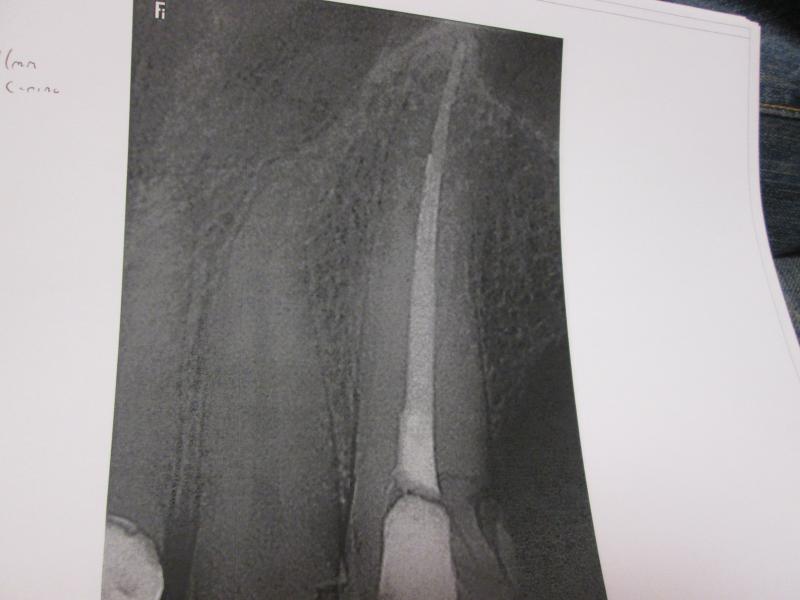

DR JET LOVES ROOT CANALS

General Dentist,  Performs Root Canals ONLY - Microscope Trained Dentist

"DR. JET'S MISSION IS TO PERFORM  ROOT CANALS FOR A REDUCED FEE USING THE LATEST TECHNOLOGY  AND TECHNIQUES TO SERVICE THE MANY PEOPLE WHO ARE UNINSURED OR UNDER-INSURED GIVING EVERYONE AN OPPORTUNITY TO SAVE THEIR TOOTH!"

ROOT CANALS by DR. JET (Jetepon Chiranand DDS)